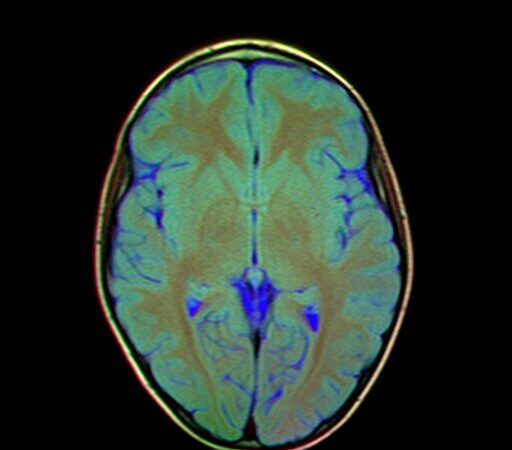

Magnetic Resonance Imaging of the brain is essential for understanding structural and functional changes within the central nervous system. Marris Medical offers high-quality imaging designed to detect subtle abnormalities that may impact cognitive or neurological health. With fast, comfortable scan experiences and highly trained specialists, we ensure precise evaluations for every patient.